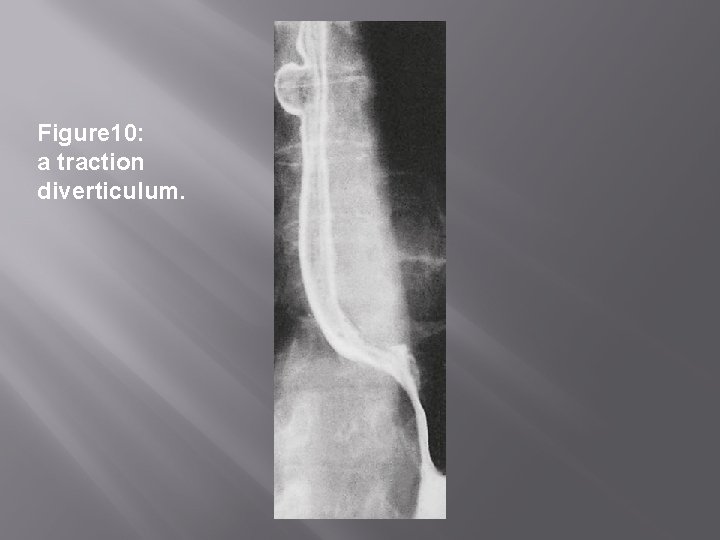

Pharyngeal and esophageal diverticula PULSION DIVERTICULA � � � False diverticula More common Result due to rise in pressure, at a weak point. TRACTION DIVERTICULA � � � True diverticula Less common Due to granulomatous disease affecting the tracheobroncheal L, Ns.

Figure 10: a traction diverticulum.